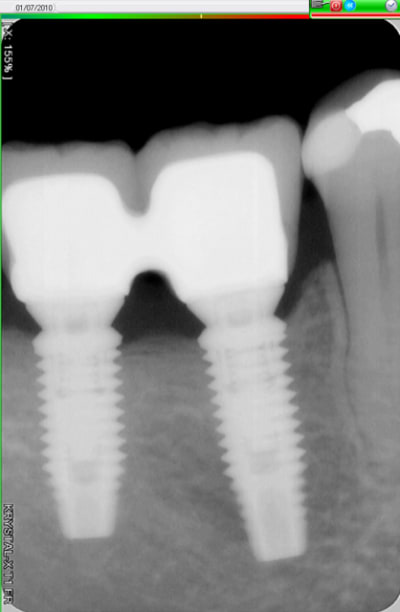

Voici trois Rx : cratère ou pas ? quel taux d'échec à 5 ans (tout les implants), ce sont les mêmes : 3I plateforme plate, deux temps chir, pas de plateform switching, pilier vissé prothèse scellée, 3 mois d'OI.

Crat 1 k8pnfh - Eugenol

Crat 2 ra8vyw - Eugenol

Crat 3 hpsffn - Eugenol

j'ai posé deux easy avec le biseau enfoui dans l'os. A 3 mois, pose des piliers de cicatrisation et un mois plus tard pose de la prothèse.

manifestement l'os ne reste pas en place à ce niveau

je prendrai un cliché dans 3 mois pour évaluer ce qu'il advient de la zone mésiale du col de l'implant distal.

46 47 xvjblf - Eugenol

46 47 pose kiaay7 - Eugenol